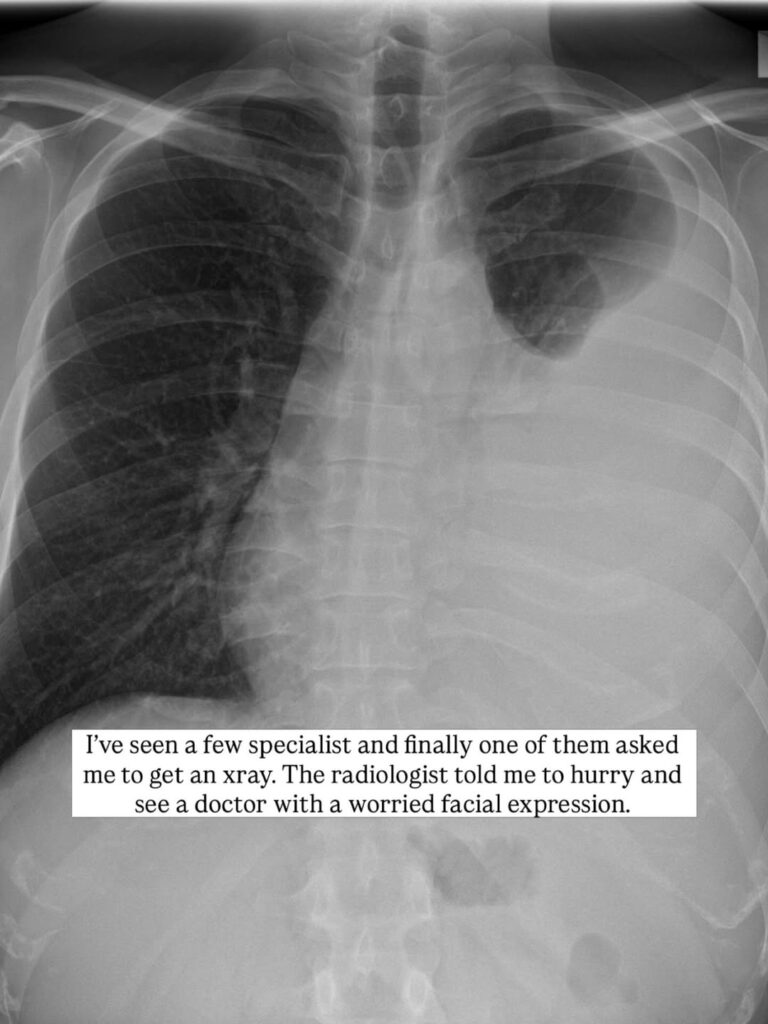

Bimbang tentang batuk yang berterusan, dia mendapatkan rawatan perubatan dan menjalani imbasan X-ray dada.

"Ahli radiologi memberitahu saya untuk segera berjumpa doktor. Selepas melihat imbasan X-ray, doktor memberitahu keseluruhan paru-paru kiri sudah dijangkiti dan dipenuhi air, menyebabkan sebahagian daripadanya tak dapat berfungsi. Mereka berkata ia mungkin kanser atau Tibi di samping meminta saya untuk berdoa ia adalah Tibi," katanya.